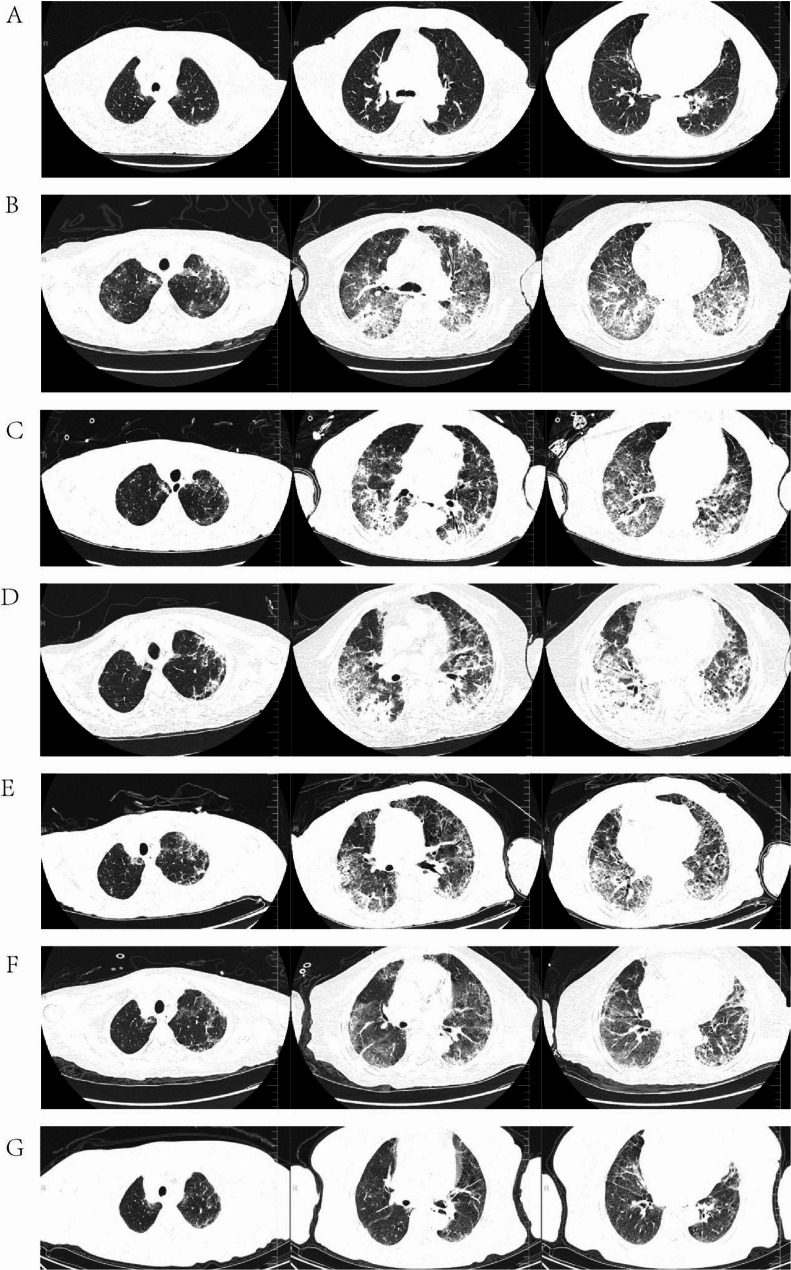

Interstitial lung disease induced by Toripalimab combined with disitamab Vedotin in upper tract urothelial carcinoma: a case report and literature review.

托利帕利单抗联合地西他单维多汀治疗上尿路上皮癌致间质性肺病1例并文献复习。